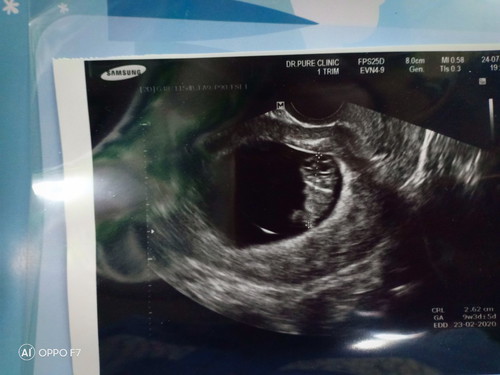

9 สัปดาห์ 3 วัน

9 สัปดาห์ 3 วัน ตัวเล็กมีความยาว 2.62 ซม. ความรู้สึกที่เห็นตัวเค้าขยับดุกดิกอยู่ในท้องมันเป็นคว่มสุขที่อธิบายไม่ถูกเลยจริงๆ